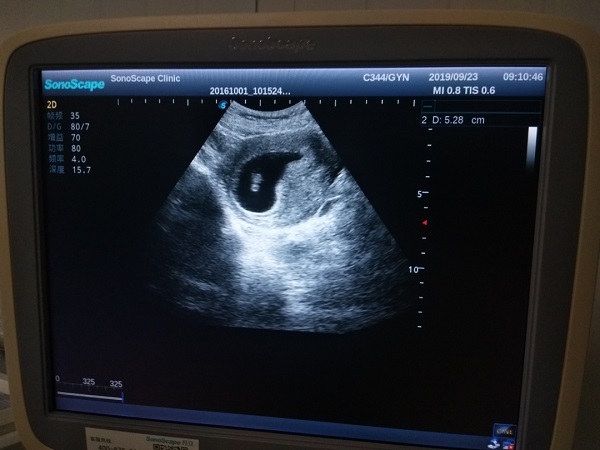

移植21天孕囊大概在1.2到1.5CM正常,具體的數值需要根據個人的身體狀況進行決定。個人體質不同,遺傳因素不同,所以孕囊的大小也會有所差異。在進行移植後要多注意休息,避免身體太過勞累,同時也要服用葉酸,可有效降低胎兒出現畸形的現象。還需定期去醫院進行孕檢。試管囊胚移植21天做b超一般能看到孕囊,但看不到胎心胎芽。不過由於每個患者的身體情況不同,胚胎著床時間也有一定的差異,所以若是囊胚移植後著床較早的話,也可能出現21天能看到胎心胎芽的情況。而若是囊胚著床較晚的話,也可能會出現孕囊和胎心胎芽都看不到的情況,這種情況一般建議患者可以耐心等待一週後再進行B超複查,確定宮腔內是否有孕囊,如果有孕囊說明女性宮內孕,如果複查還是沒看到孕囊的話,可能就有問題了,需要結合hcg和孕酮的變化來判斷移植是否成功。

移植通常指的是胚胎移植,移植21天一般可以看到孕囊,但看不到胎心胎芽,一般需要等到30天以後,且由於胚胎著床的早晚和發育的快慢不同,所以沒有一個確定的胎心胎芽可見的具體日期。以下是對囊胚移植21天是否能看到孕囊和胎心胎芽的分析:

囊胚移植第21天相當於正常懷孕38-41天左右,而對於月經週期比較規律女性來講,一般懷孕35天左右可以觀察到孕囊,而對於一些月經週期本身比較長的女性來說,在移植後21天通過b超並不能夠看見孕囊,因此也需要延長做B超檢查的時間,這個階段也需要結合化驗血hcg及孕酮,來判斷體內的激素水平是否符合懷孕時間,可以在醫生的指導下定期的檢查,這個期間也需要補充葉酸片,注意營養均衡。

胎心胎芽一般在孕6~7周出現,在移植的時候一般是移植3天的鮮胚或5天的囊胚,在移植囊胚後30天也就相當於停經49天也就是孕7周,如果胚胎髮育好應該可以看見胎芽、胎心,如果移植後28~30天沒有看見胎芽、胎心,建議1周後複查超聲,如果還是沒有胎芽胎心就有可能胎停育了。